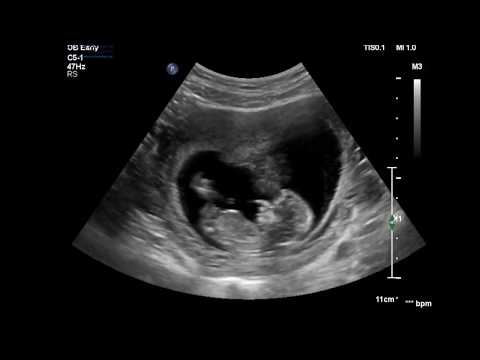

It's not usual to have a dating scan early in your pregnancy to work out how many weeks pregnant you are and your due date . However, you may need a scan in early pregnancy if you have complications such as bleeding . Sometimes other scans are carried out to check the growth of your baby or the position of your baby or the placenta . You will need extra scans if you're carrying twins or if you have had complications in this pregnancy or a previous pregnancy .

The purpose of the scan is to confirm viability, accurately establish gestational age, determine the number of viable fetuses, evaluate gross fetal anatomy and, if requested, assess the NT as part of the risk assessment for aneuploidy . Indications for early pregnancy scans (less than 12 weeks) Indications include:

An early pregnancy dating scan , when compared with scans later in pregnancy, can be more accurate when assessing the expected date of delivery . With maturity, the size of the baby correlates less to its age than in the early weeks . Why would I need a 7 weeks pregnant scan ? To see if one or more babies are present and assess gestational age .

The scan is optional and not everyone will have it . You can discuss whether you want or need a dating scan with your doctor or midwife . A dating scan is usually done to check how many weeks' pregnant you are, but can be done for other reasons, such as if you have had bleeding during your pregnancy or you have had previous miscarriages . If you choose to have a dating scan , it will most probably be your first scan . You will need to get a referral from your doctor or midwife for a dating scan .

Pregnant women should be offered an early ultrasound scan between 10 + 0 and 13 + 6 weeks to establish accurate gestational age . (Grade A recommendation) Ultrasound assessment of embryonic/fetal age ( dating ) uses the following assumptions: